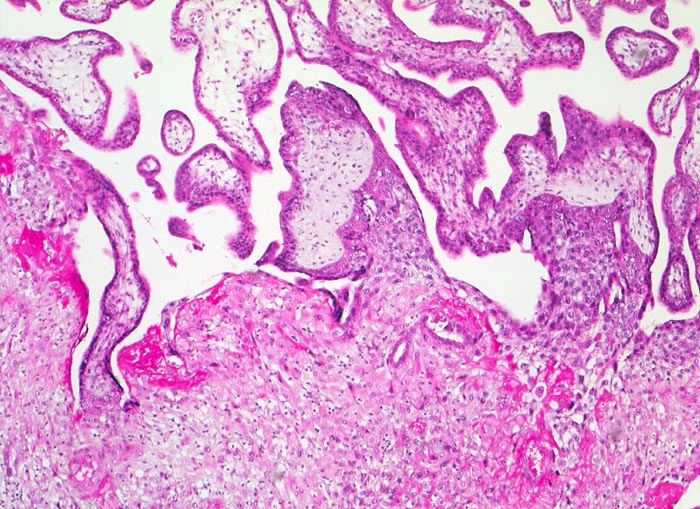

PathoPic ID 5207 - Gravidität

Gravidität

Plazenta

Grosszellige

Dezidua basalis. Darin verankert sind ein Teil der Zotten, die

Haftzotten.

Proliferierender Zytotrophoblast der Haftzotte.

Fibrinoid.

11. Schwangerschaftswoche. Normale Schwangerschaft